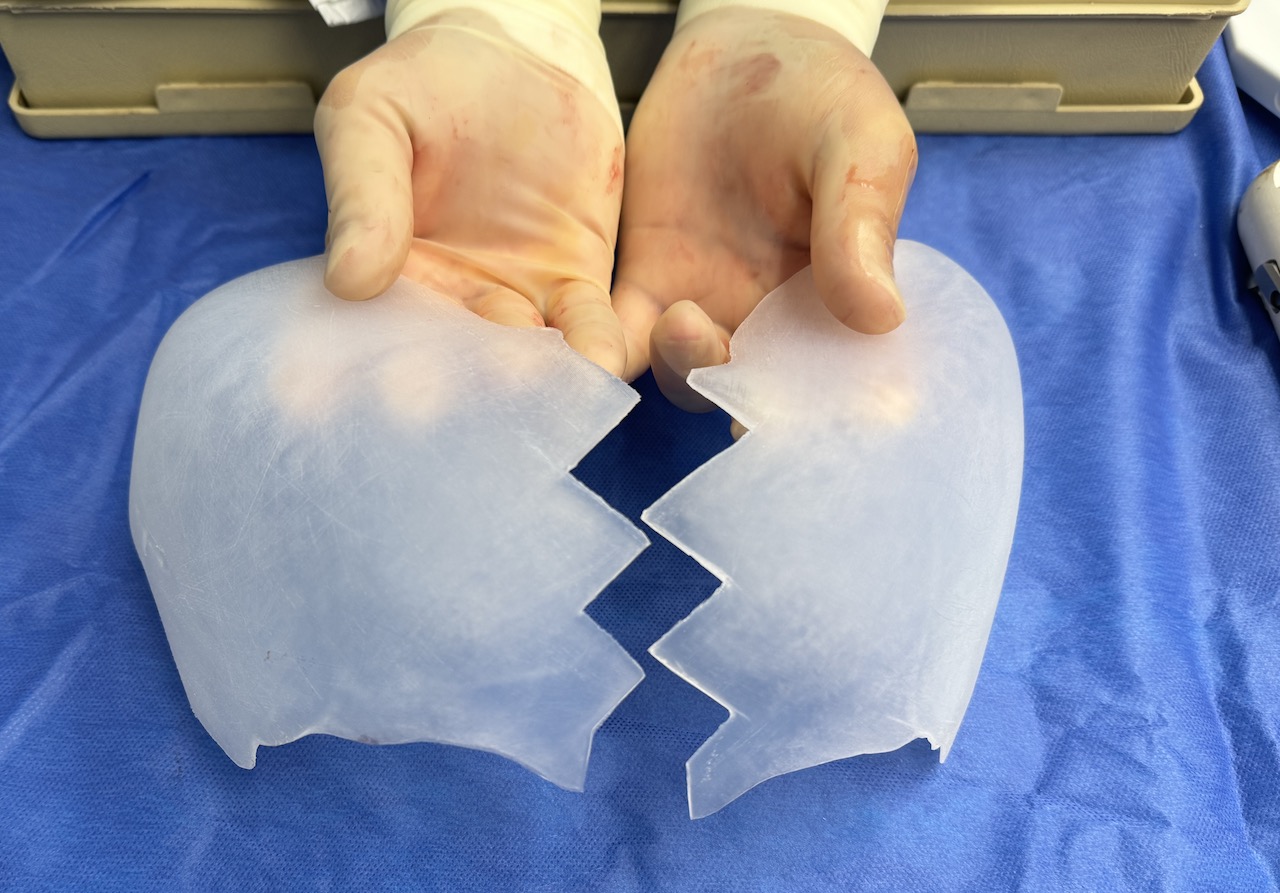

Desire for major head reshaping with a taler and wider head shape.

Placement of large two piece custom skull implant through a sagittal scalp incision.

Desire for major head reshaping with a taler and wider head shape.

Placement of large two piece custom skull implant through a sagittal scalp incision.